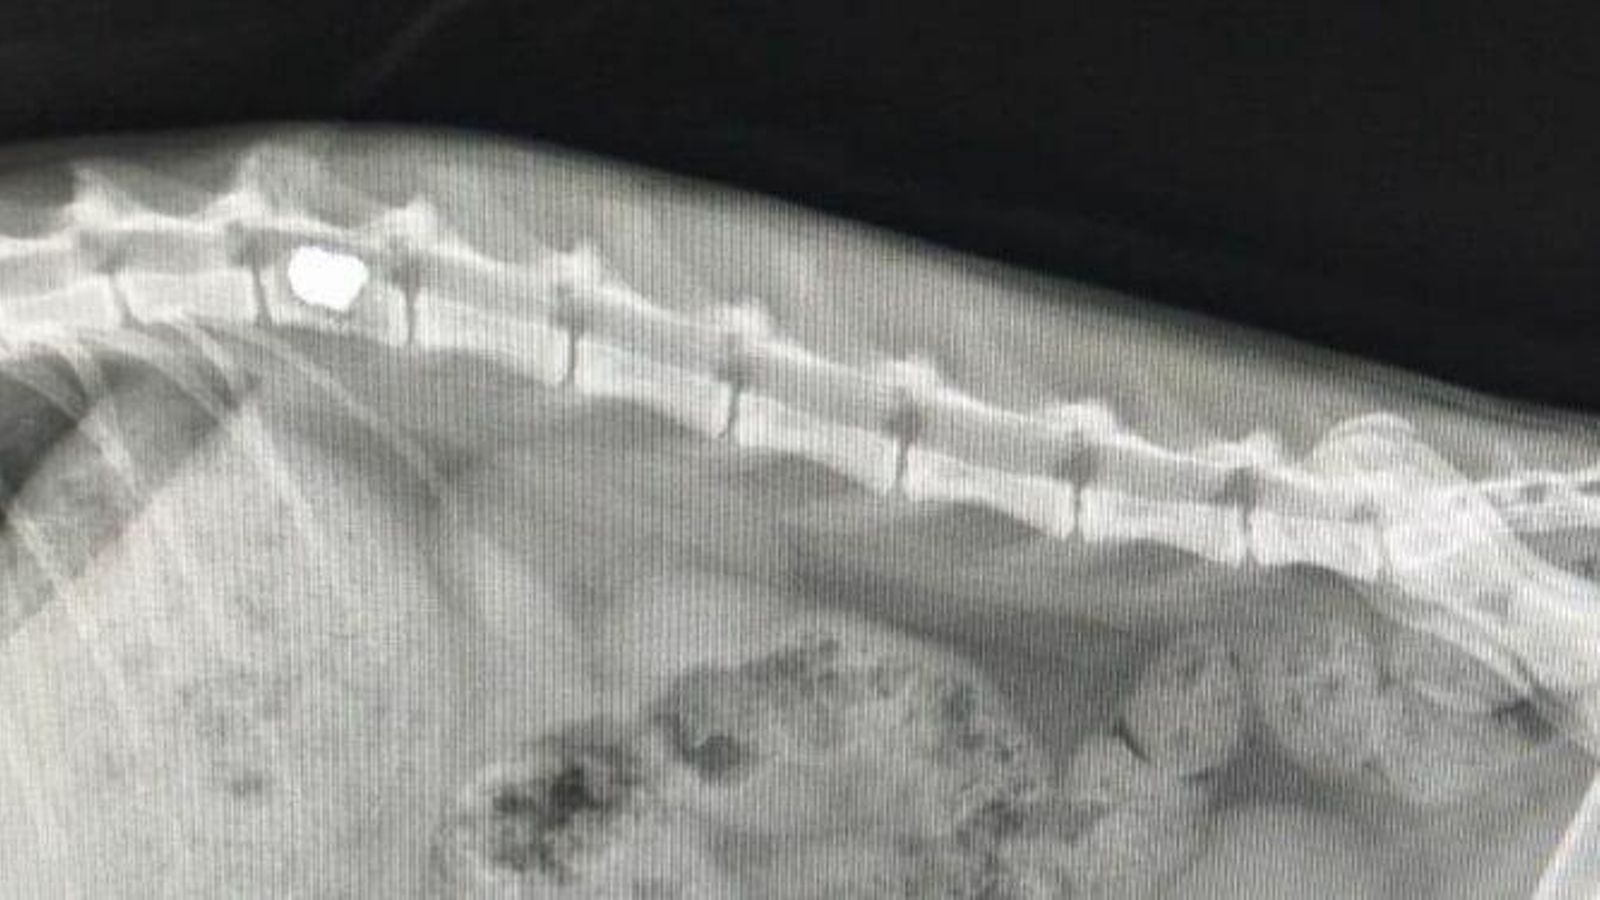

Para sorpresa de todos, las radiografías mostraron que Abad, como lo llamaron los voluntarios, tenía una bala alojada en la columna, en plena médula. Además, por la cantidad de deposiciones que acumulaba en el intestino y lo llena que se encontraba la vejiga, se calcula que el animal llevaba herido entre cinco y seis días. “Además, la herida estaba cicatrizando”, apunta Carmina González.

Radiografía del gato tras el disparo.